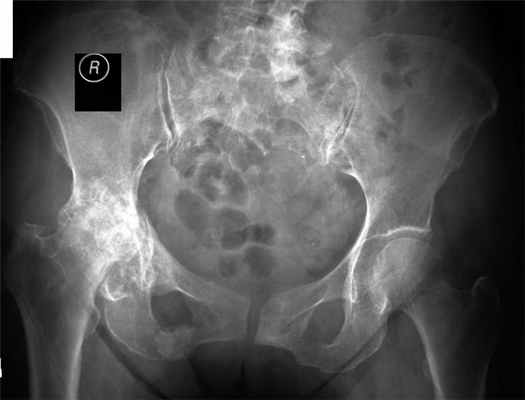

При II стадии деформирующего артроза боли локализуются уже в тазобедренном суставе С иррадиацией в поясничную область и коленный сустав. Клинически наступает умеренная атрофия мышц бедра, ограничение отведения бедра в сторону, при движениях отмечается хруст в суставе, боль при пальпации в паховой области в проекции суставной щели. Сгибание и разгибание в суставе не ограничены. Рентгенологически отмечаются костные разрастания по краю вертлужной впадины, иногда деформация головки бедренной кости, могут быть дегенеративные кисты.

Рентгенологически отмечается сужение суставной щели, деформация головок бедренной кости, массивные костные разрастания но краям суставных поверхностей.

Для постановки диагноза достаточно выполнить обычную рентгенографию тазобедренного сустава. По снимку можно будет увидеть сужение суставной щели, то есть оценить, насколько истощена хрящевая ткань. Также специалист проводить клинический осмотр, где с помощью функциональных проб делает выводы об объеме движений. Иногда в редких случаях может понадобиться проведение МРТ, КТ или УЗИ тазобедренного сустава.

При коксартрозе 3 степени на рентгене видно значительно суженую суставную щель. Болевые ощущения интенсивные, сустав деформируется – развивается дефартроз тазобедренного сустава. На таком этапе, как правило, нехирургические методы лечения неэффективны. Необходима замена тазобедренного сустава (эндопротезирование).